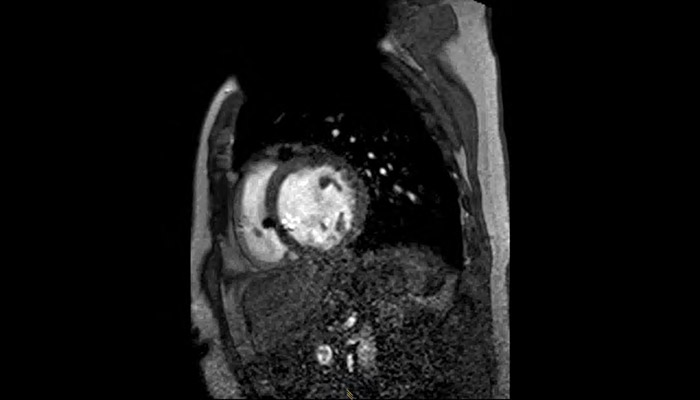

MR Conditional ICD

MRI of heart with MR Conditional ICD

A patient with an MR Conditional ICD and suspected myocarditis presented for MRI. This short axis view of the heart is created with an SSFP (steady state free precession) sequence on a Philips Achieva 1.5T system. The cardiac MRI exam reveals normal dimensions and regular function of the right and left ventricle. Note the ICD lead in the right ventricle (arrow) and the signal void in the left pectoral region, indicating the ICD-IPG (asterisk). Courtesy of Dr. Sommer.